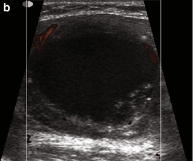

Uniformly enlarged thyroid

Hypoechoic

Heterogeneous echotexture

Hypervascular (‘Thyroid inferno’)

Differential = Hashimoto’s Thyroiditis